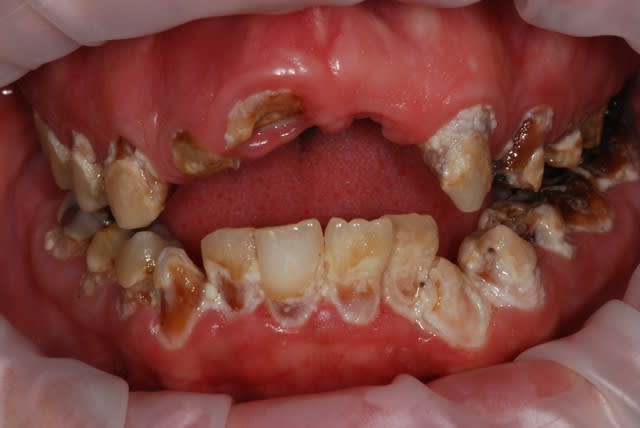

Pépélaratiche

Céramik écrivait:

> Bonjour, c'est pour un nettoyage...

> Le noir , il va partir ?

> Douleur ? non , pourquoi ?

> Des caries? non, je pense pas.

> Les dents cassées ?

> Ben elles tombent, c'est comme cela dans la famille, ont a pas des dents

> solides...

> Je dois partir dans 30 minutes, j'ai un autre rdv...alors pour le noir ?

>

> Avec du dentifrice blanchissant, ça devrait aller...

Tu lui fais deux beaux complets amovibles et tu verras même ça il en fera de la merde